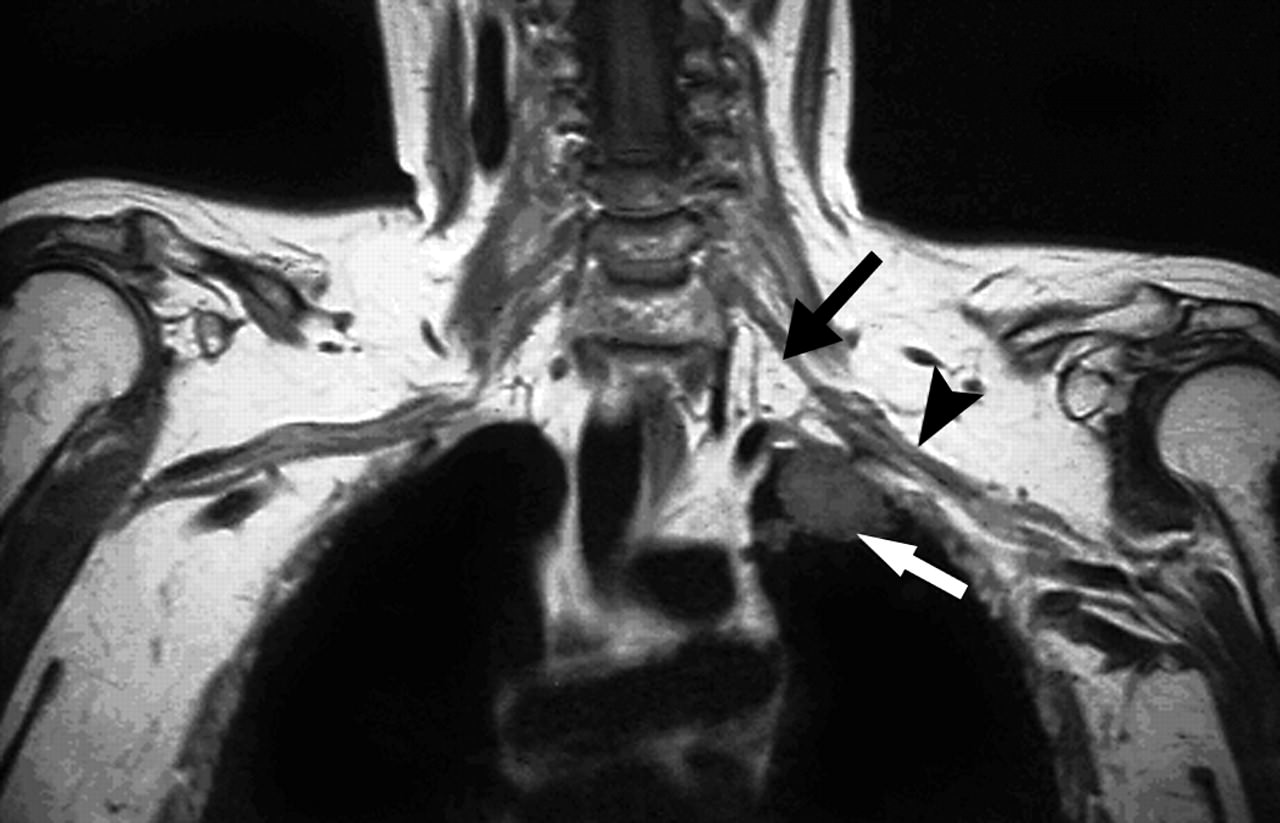

Под таким названием в онкологии известна опухоль верхушки легкого. Имя американского врача Генри Панкоста получила не только сама опухоль, но и один из комплексов симптомов (синдром), развивающихся при ней.